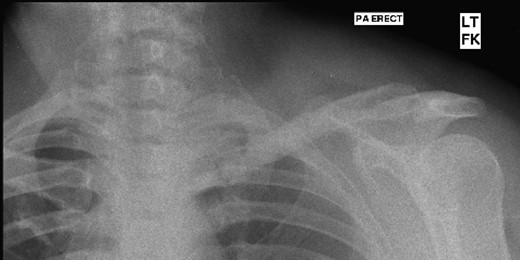

Four years following the procedure, after discomfort in her shoulder, X-rays revealed that the plate had broken and there was a fracture of the clavicle. This plate was subsequently removed and an underlying non-union was found, but no evidence of recurrence of the tumour. She has been managed symptomatically since and has a full range of shoulder movements but some discomfort when doing heavy lifting, which she therefore avoids (Figs 5 and 6).